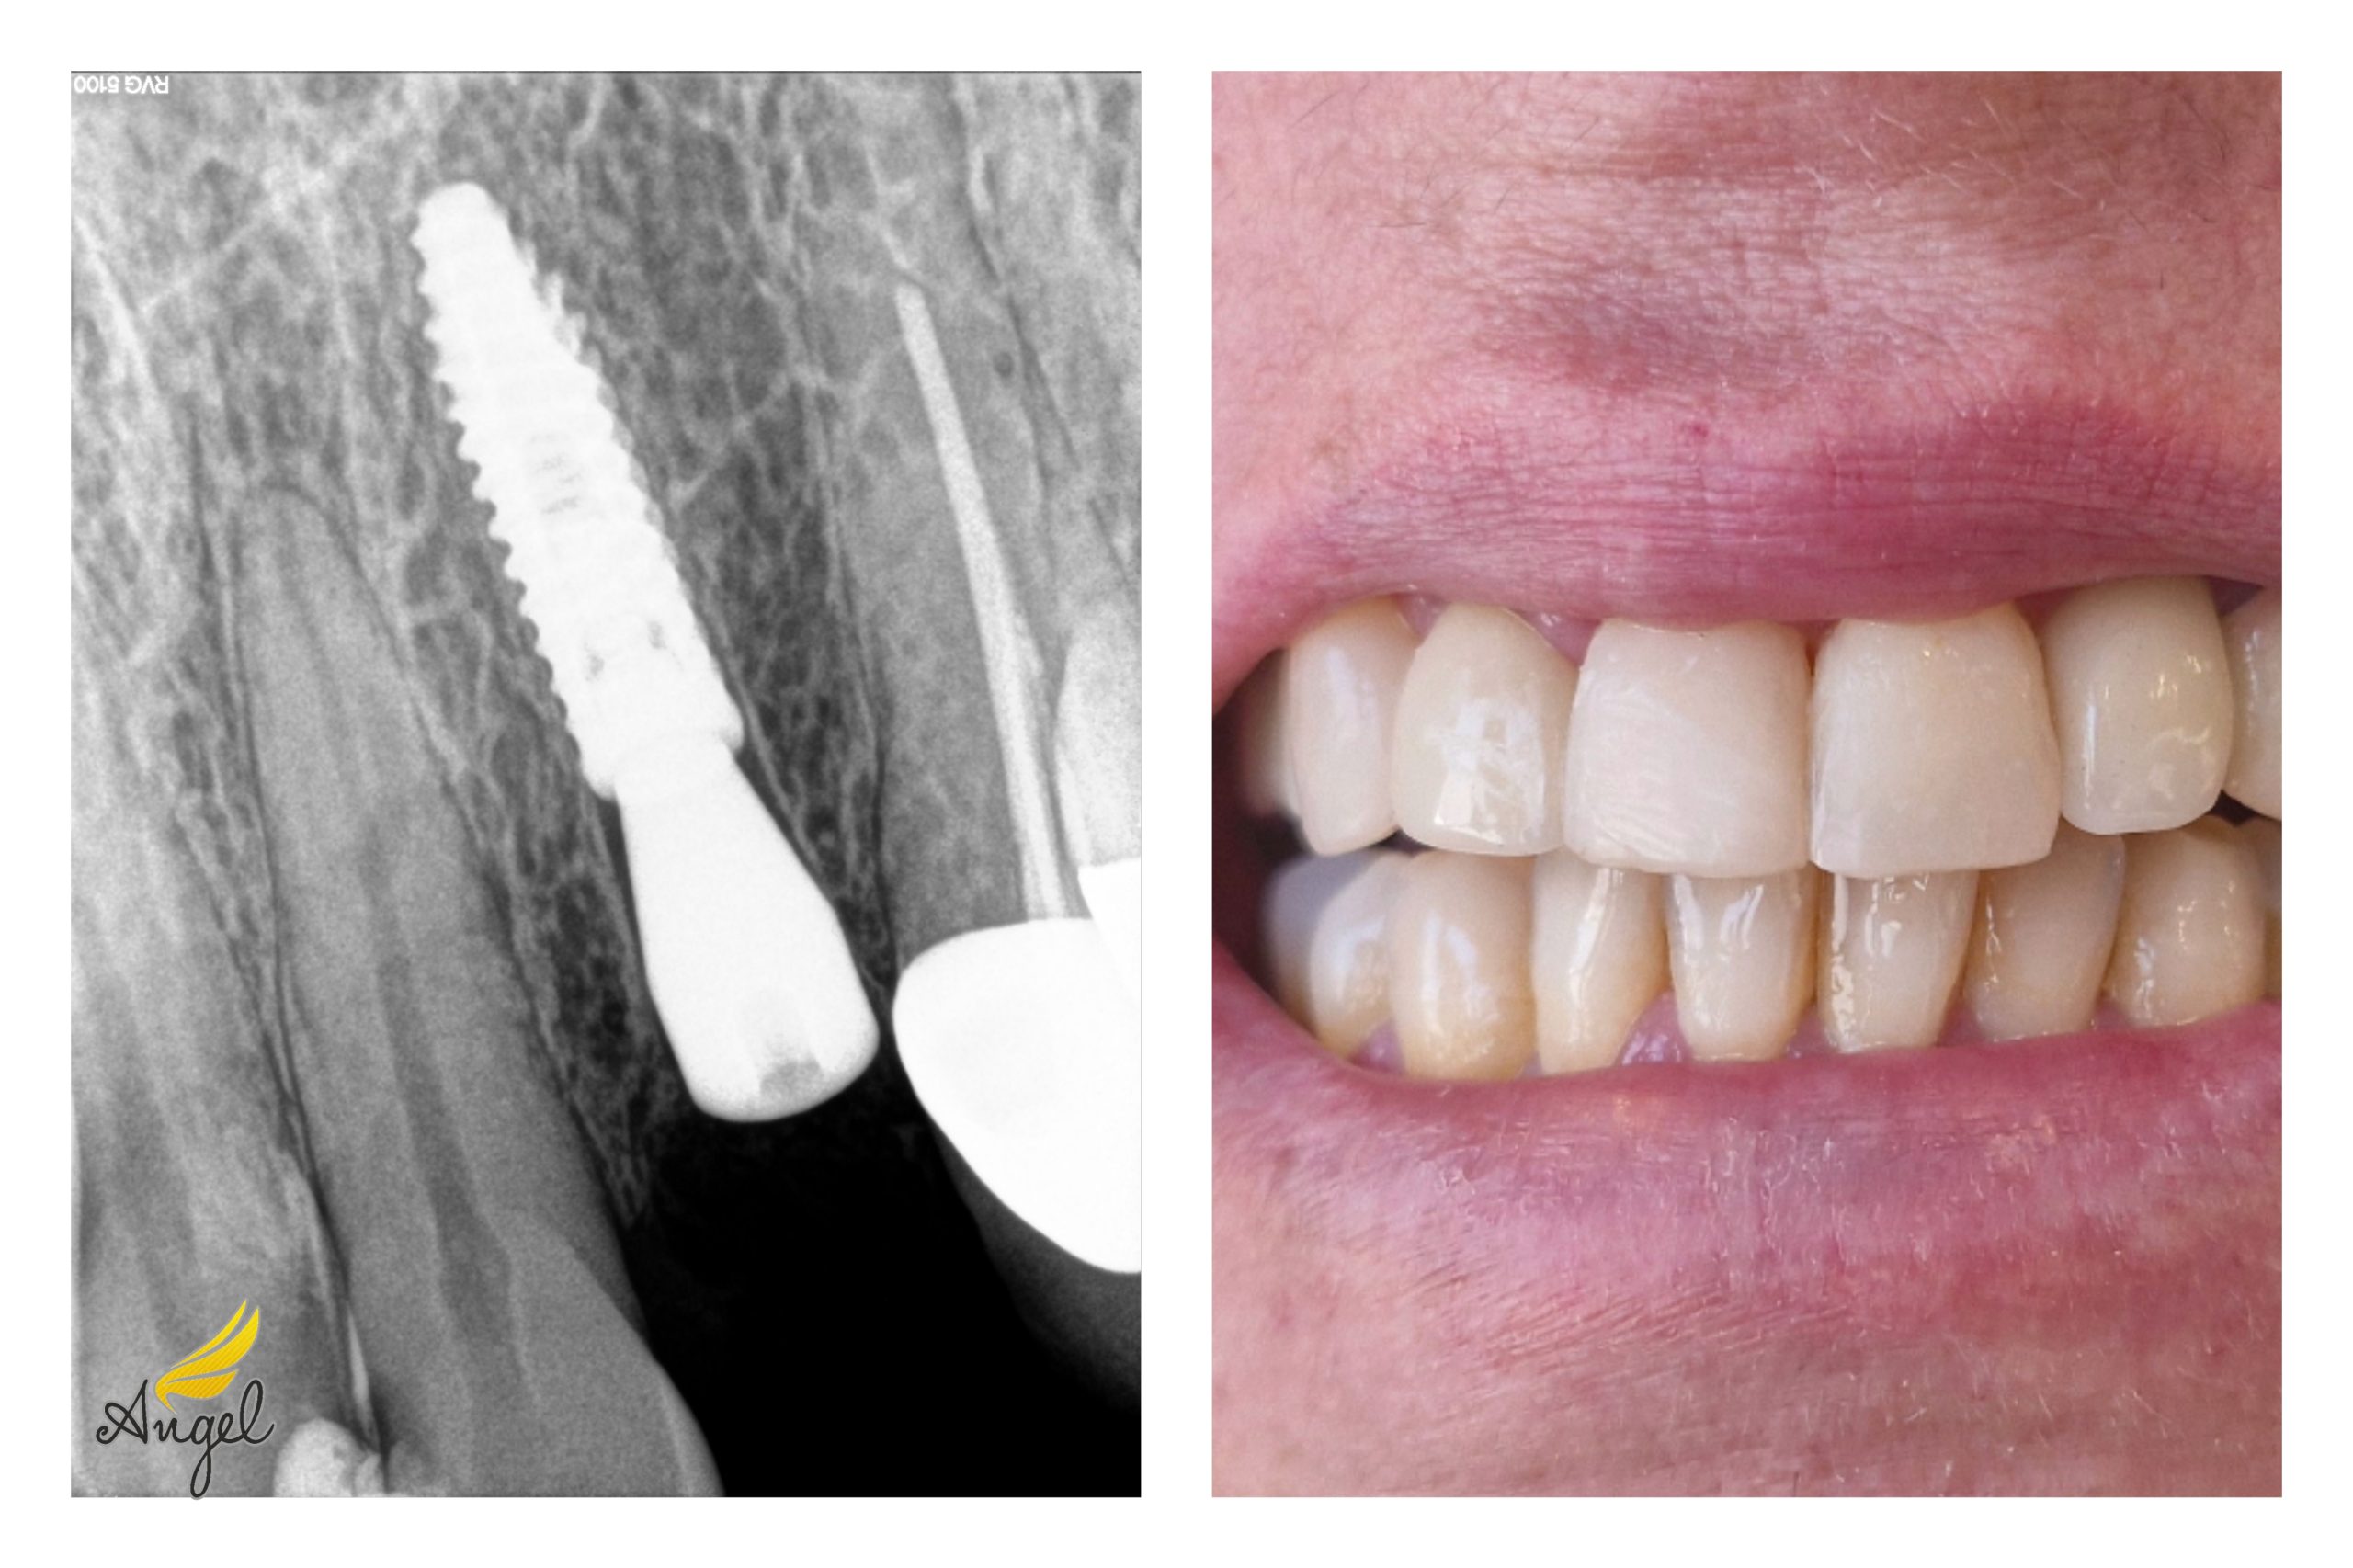

تغذيه ورژيم لاغری، رژيم بيماران قلبی وديابتي مراقبتهای پوست، بوتاكس ، مزوتراپی، ايمپلنت، كليه خدمات دندانپزشكی از جمله:لمينيت، ایمپلنت و…